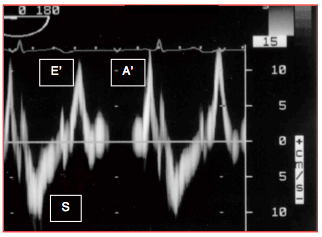

- La vélocité des mouvements de structures tissulaires comme l'anneau mitral ou un segment myocardique. La systole est caractérisée par un déplacement S' de vélocité 10-15 cm/s, bien corrélé à la FE [27]. La diastole est marquée par deux évènements sur la courbe de vélocité tissulaire: la relaxation protodiastolique E' et la contraction auriculaire A' (Figure 25.182). Après réglage de la machine sur la fonction Doppler tissulaire (DT) et sur une émission de basse fréquence (≤ 4 MHz), la fenêtre du Doppler pulsé est ajustée au niveau de l’anneau mitral avec une ouverture de 5-10 mm ; l’échelle des vélocités est de 15-20 cm/s. L’axe du Doppler est positionné aussi parallèle que possible au déplacement mitral, parfois en modifiant légèrement l’angle du capteur. La position la plus habituelle est la partie latérale de l'anneau en vue 4-cavités 0-20° (8-12 cm/s). La vélocité S' est un peu plus basse au niveau septal. La routine est de moyenner ces deux valeurs sur 3 échantillons successifs.

Figure 25.182 : Courbe des vélocités de l'anneau mitral latéral au Doppler tissulaire traduisant la contraction-relaxation longitudinale du VG. S: contraction systolique. E': relaxation protodiastolique. A': contraction auriculaire. Pour les trois mouvements, la Vmax normale est de 10-15 cm/s.